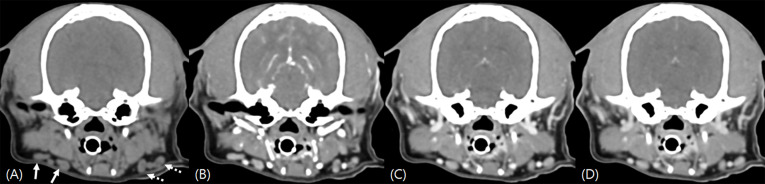

An 11-year-old Bichon Frise presented with a right cervical mass. Computed tomography revealed a thyroid mass without significant lymphadenopathy; however, the caudal portion of the ipsilateral retropharyngeal lymph node exhibited marked hyperattenuation on pre-contrast images. Histopathology of this lymph node confirmed the presence of metastasis from thyroid adenocarcinoma. The caudal portion of the lymph node displayed dense tumor cells with abundant sodium/iodide symporter-positive cells. The observed hyperattenuation of the lymph node was presumed to result from iodide deposition associated with the metastasis of the thyroid tumor. This case suggests that even in the absence of lymph node enlargement, hyperattenuating lymph nodes should raise suspicion for metastasis in dogs with thyroid tumors. However, as this is a single case, further studies are needed to determine the broader applicability of this finding.

Abstract Image